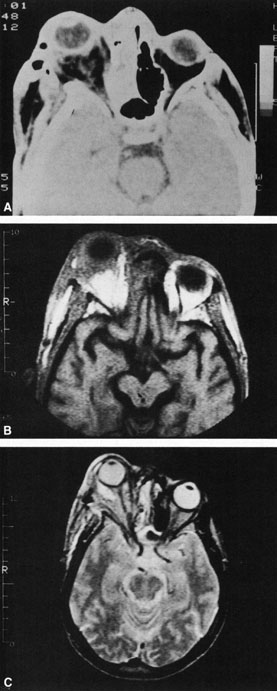

A subperiosteal abscess may rupture or invade the periorbit, resulting in an orbital abscess. This may or may not be contiguous with the subperiosteal collection on CT. There may be gas or air–fluid levels within the mass.51,56,58,59 An orbital abscess may present as an enhancing ringlike peripheral mass that can be either heterogeneous or homogeneous (Fig. 18).

Fig. 18. Orbital abscess. A. Computed tomography of an orbital abscess presenting as an enhancing intraconal mass on right side. B. T1-weighted image. C. T2-weighted image. Note area of high signal corresponding to abscess.

Magnetic resonance imaging (MRI) is purported to be more useful than CT in the diagnosis of preseptal cellulitis. It is less reliable at diagnosing the subtle signs of muscle enlargement and periscleritis and thus is not as useful in differentiating orbital cellulitis from other inflammatory orbital diseases.71 On MRI with gadolinium contrast, orbital cellulitis may show a smearing or linear streaking of the normal fat shadows on T2-weighted images. MRI is excellent for demonstrating localized fluid collections such as abscesses. It is not helpful in distinguishing a transudate from an exudate, because both appear liquid and are of low intensity on T1-weighted images and bright on T2-weighted images (Fig. 19).

MRI is superior to CT in the diagnosis of cavernous sinus thrombosis. T2- and proton-weighted images show high signal luminal narrowing as well as absent flow or localized parenchymal infarcts (Fig. 20).72 Absent flow can be demonstrated as well in the superior ophthalmic vein in cases of carotid or cavernous sinus thrombosis.72 MRI with gadolinium can help define these abnormalities and can detect dural invasion.

Fig. 20. Cavernous sinus thrombosis. Axial T1 image shows cavernous carotid luminal narrowing on right and enlargement of right cavernous sinus. Note extensive sinus disease.